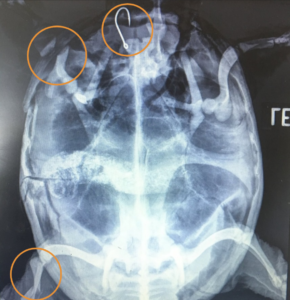

Tina Batak is a student who shared her experience as an intern at the WMC this summer. A snapping turtle with a shell fracture was brought in by a concerned community member. In her rounds presentation, Tina described to the students how she and the team handled this patient’s case throughout its time with us. She described how sedating the turtle calmed him down and let them better assess the injuries he sustained prior to coming to us. Additionally, she explained the medications used to control the pain and inflammation caused by his trauma. This is especially helpful for our first-year students who are just beginning to be exposed to these drugs and their applications. The turtle’s wounds were stabilized, and the team made plans to take radiographs (X-rays) to give them a better understanding of the extent of the patient’s injuries. Tina walked us through those radiographs, explaining the implications of the injuries.

This turtle had several severe fractures and a fishing hook embedded in his esophagus! Tina described the process of carefully removing the hook and stabilizing four of the shell fractures. Despite the team’s hard work at stabilizing the fractures, the severity of his injuries and his poor mentation meant his prognosis was guarded. Tina discussed the way this patient’s wound healing, activity level, and quality of life were evaluated every day, knowing that subtle changes in these assessments could give us subtle hints as to whether the turtle was going to pull through. Recheck radiographs can also be used to ensure bones are healing appropriately. Despite all of our efforts, unfortunately, this turtle’s injuries were too severe, and he did not make it. However, Tina was able to share her experience in monitoring this patient’s progress in the hopes that students will draw on her work when managing future cases.